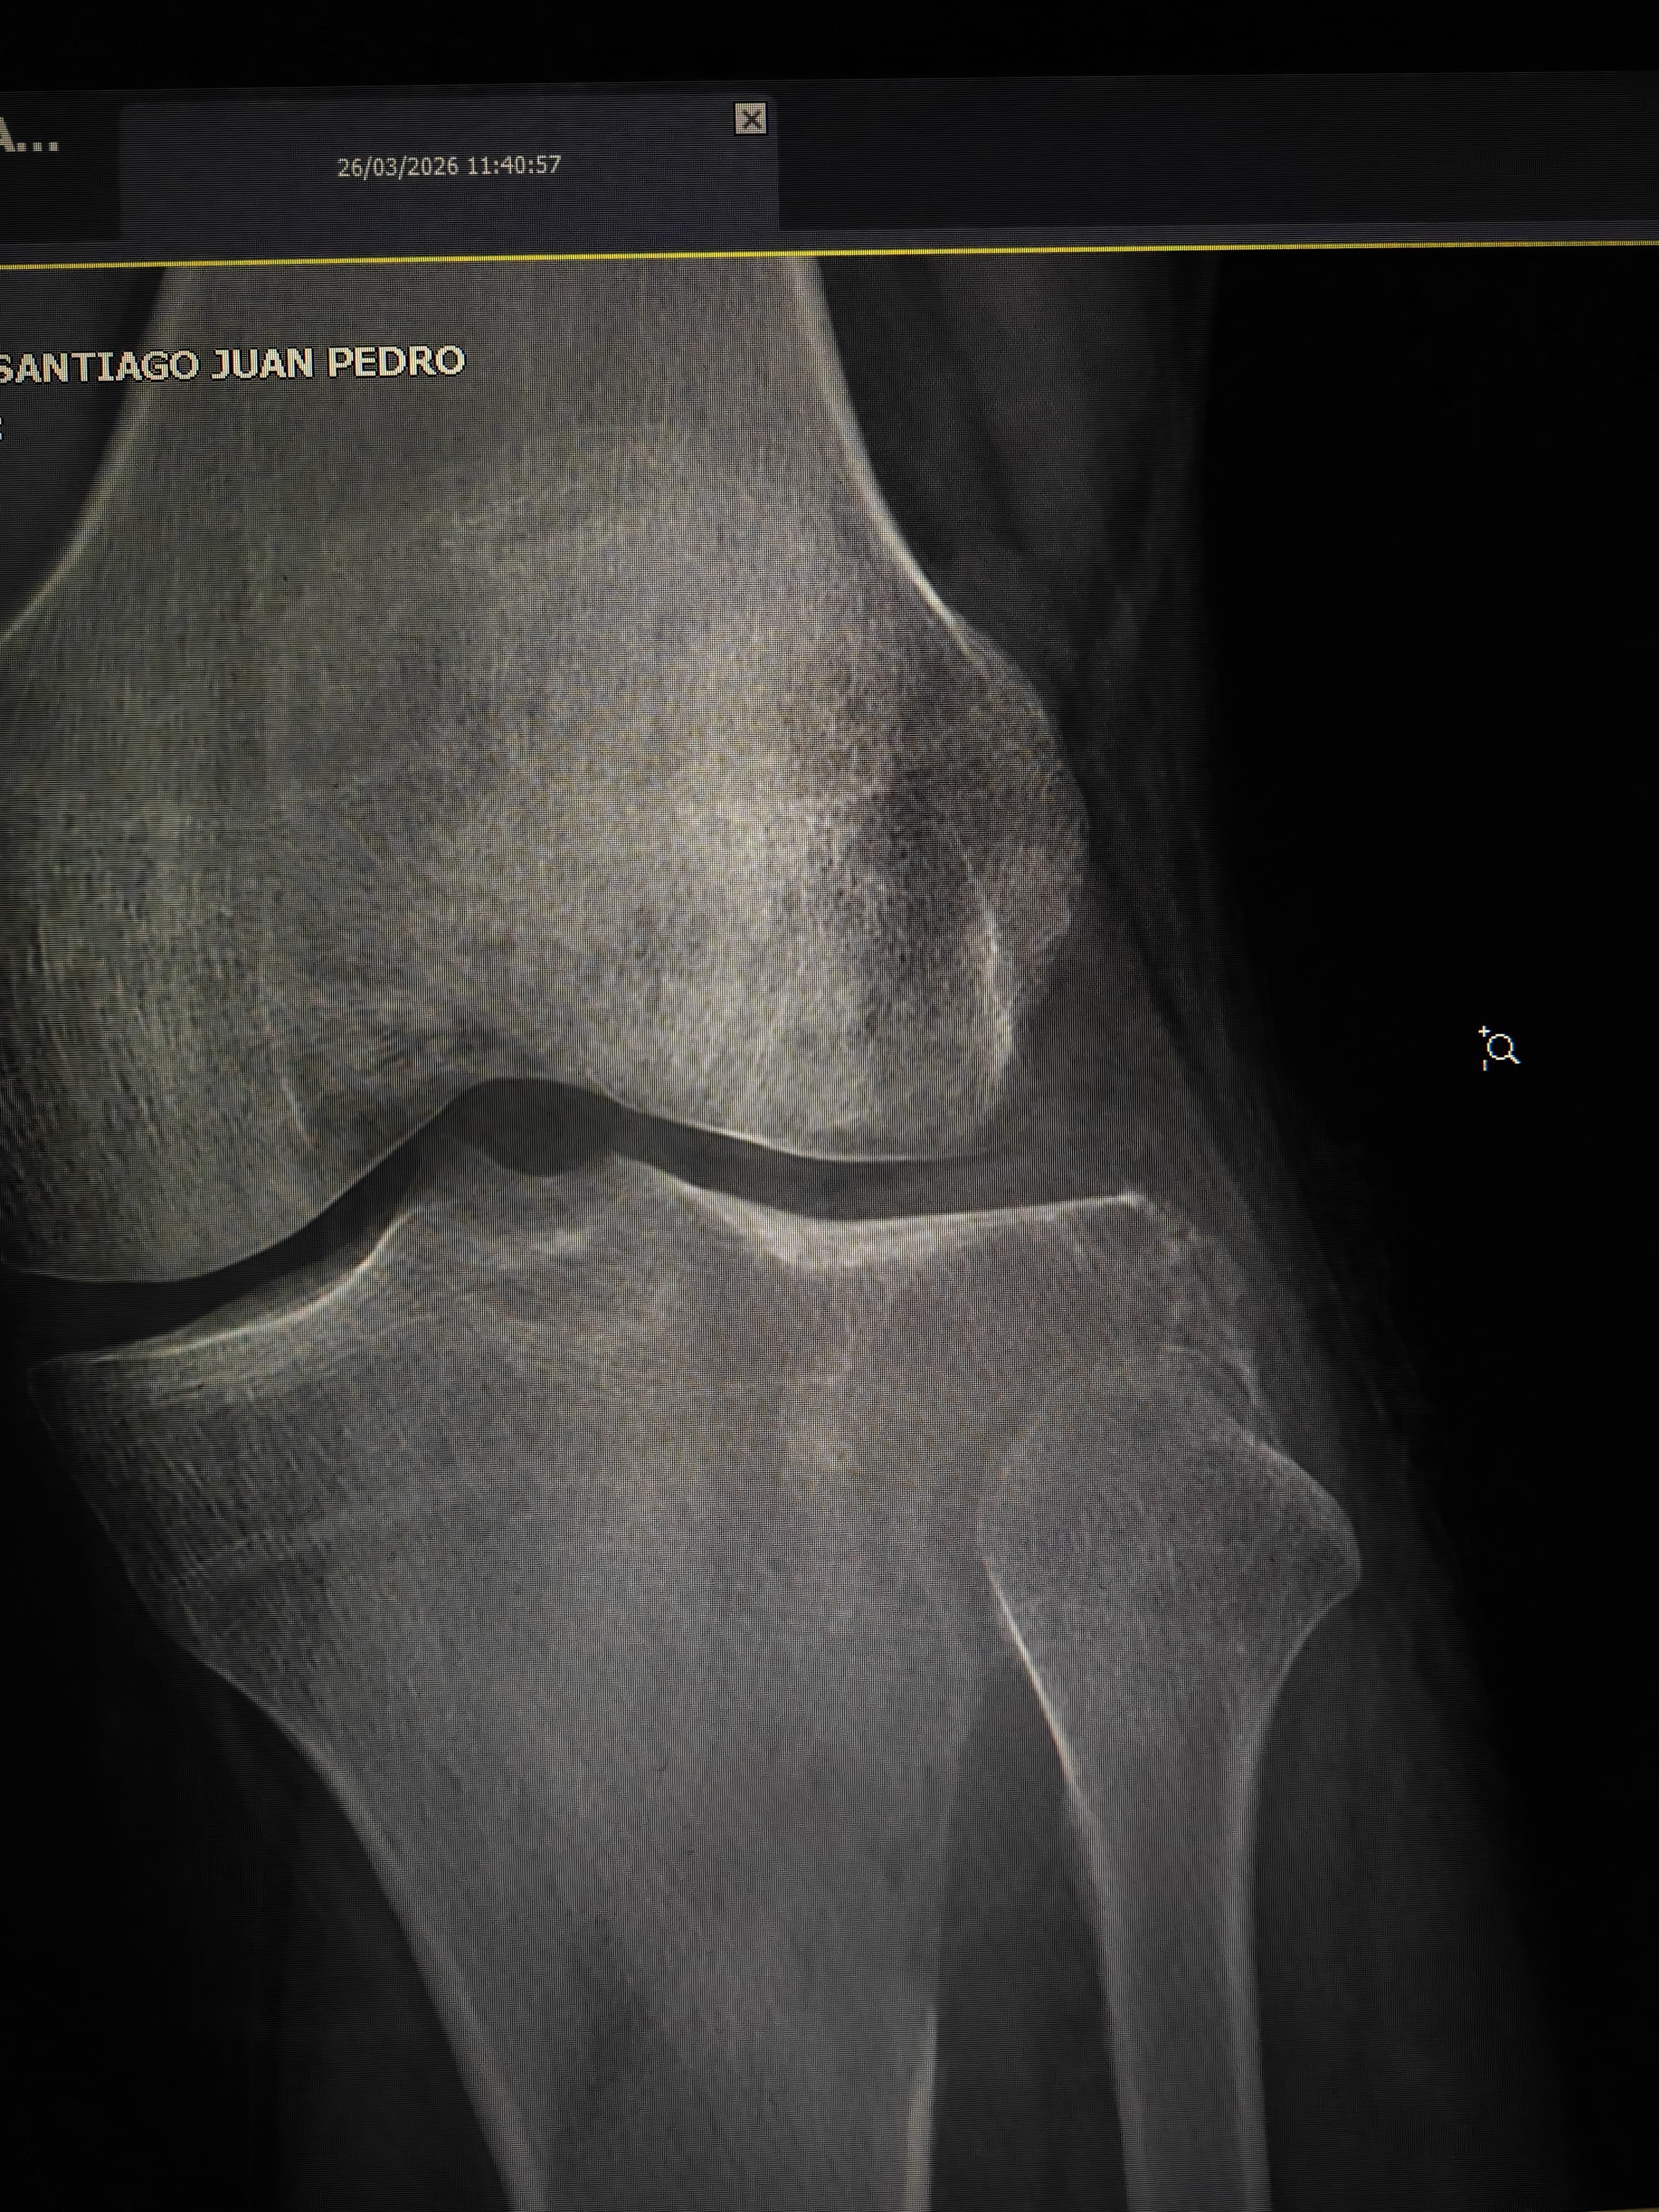

Estoy recaudando fondos para mi novio, quien actualmente tiene un tumor agresivo en la rodilla (tibia). En este momento estamos en espera de los resultados de su biopsia para conocer exactamente el diagnóstico y el tratamiento que seguirá.

salvar su rodilla y su calidad de vida.

Él es una persona joven, fuerte y con muchas ganas de salir adelante, pero el proceso médico implica estudios, tratamientos y posiblemente una cirugía que representan un costo muy alto para nosotros.